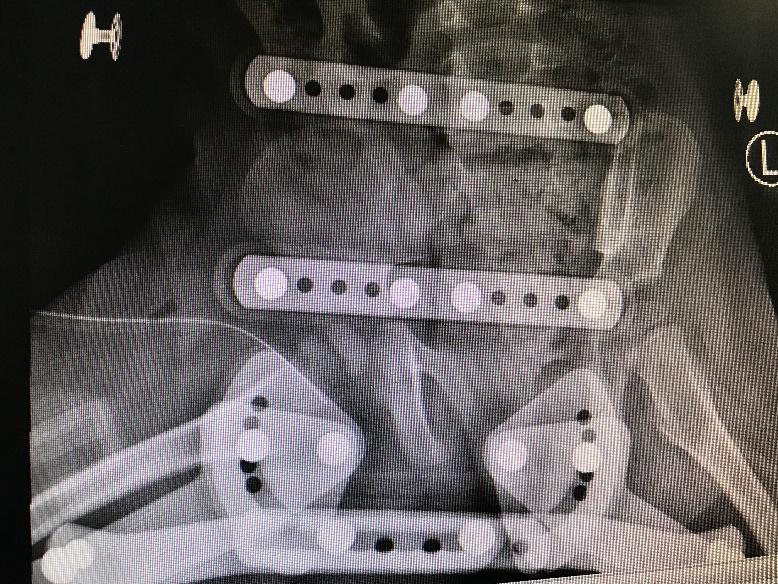

1 资料与方法 1.1 一般资料本研究为回顾性研究,获得医院医学伦理委员会审批(审编号:2020-IRB-035),通过检索本院的电子病例系统,搜索2016年1月1日至2018年12月31日期间出院诊断为“化脓性髋关节炎”的所有病例信息。纳入标准:(1)患儿临床症状、体征、影像学检查、关节液液培养、关节腔液白细胞计数(计数≥50 000 / mm3)、手术或病理证实的化脓性髋关节炎,见图 1~4;(2)关节腔穿刺或手术可见脓性标本。排除标准:(1)年龄>3岁;(2)穿刺或手术未能取得足够标本送检细菌培养者。

| 图 2 MR超示关节腔内积液 |